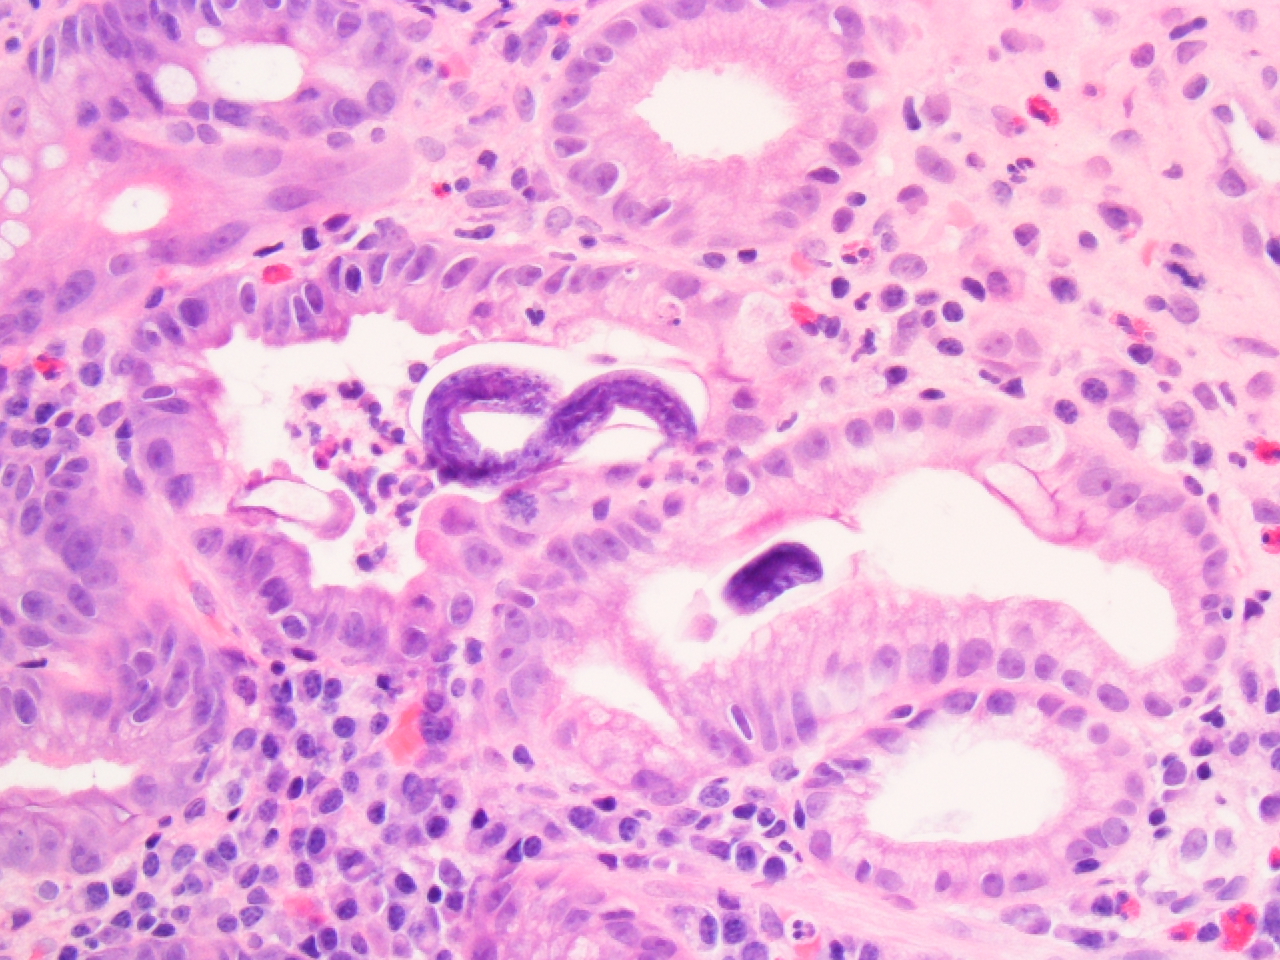

Фотографии медицинских исследований инсулиномы и синдрома Триады Уиппла